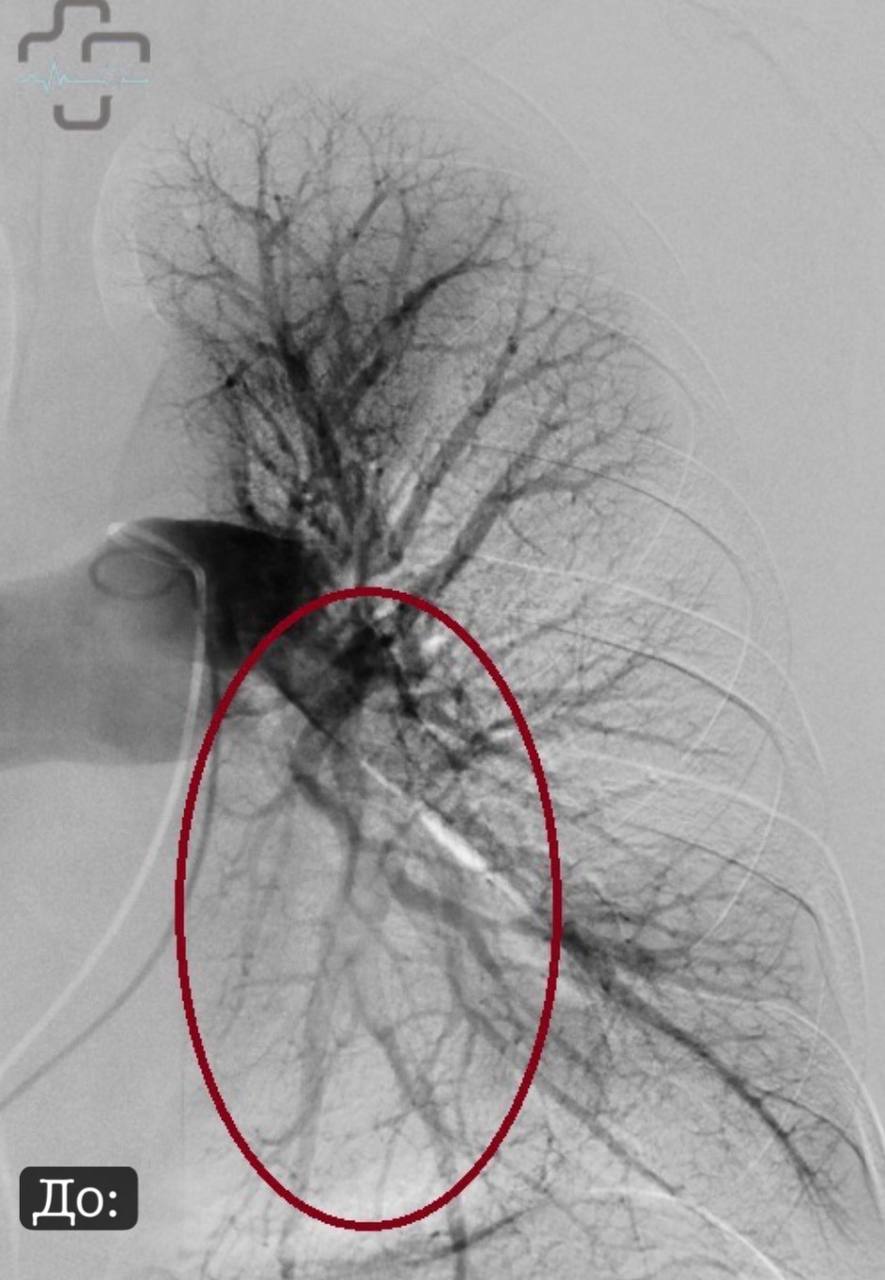

В городской больнице Орска провели уникальную операцию при тромбоэмболии легочной артерии. Это состояние, когда тромб перекрывает сосуды легких.

Пациентка из Оренбурга была переведена в Орск, где врачи применили ультразвуковой транскатетерный тромболизис — метод, который в России начали использовать только в 2024 году.

В отличие от обычного лечения, когда лекарство разжижают кровь во всем организме, новая методика работает точечно. Катетер вводят через бедренную вену прямо к тромбу, ультразвук помогает разрушить его и равномерно распределяет лекарство.